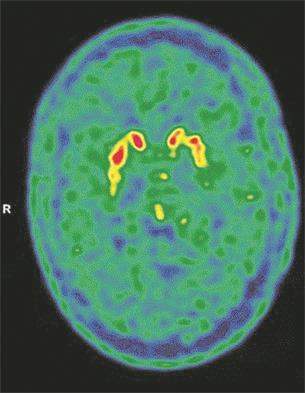

Foto: The Lancet

- Međutim, tokom izolacionog perioda od tri nedelje njegov rukopis se promenio, javile su se poteškoće u govoru, pisanju poruka na mobilnom telefonu, primetio je osećaj treperenja u desnoj ruci. Po povratku kući nastavio je da ima ove simptome i na kraju je primljen na odeljenje za neurologiju u medicinskom centru „Šare Zedek“ otprilike dva meseca nakon što je bio pozitivan na SARS-CoV-2 - navodi se u studiji i dodaje da je snimak PET skenerom pokazao promene na mozgu karakteristične za Parkinsonovu bolest, te je pacijentu dijagnostikovan parkinsonizam.